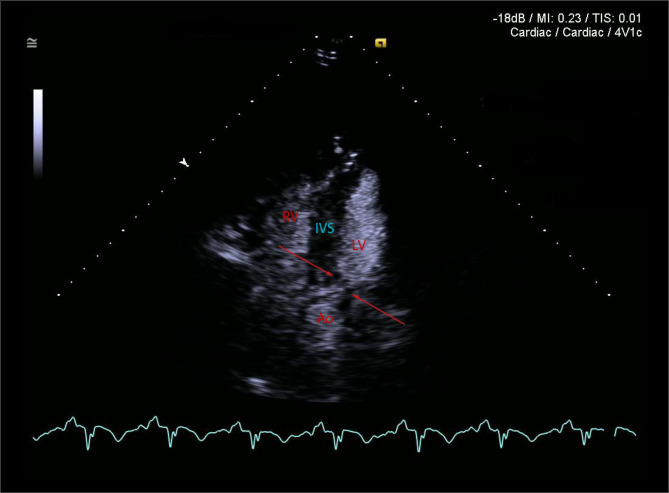

Case presentation: An 88-yo man presented with angiotensin converting enzyme inhibitor (ACEI) - induced angioedema. He received steroids and adrenaline, but progressed to the respiratory arrest, requiring emergency awake fiberoptic intubation and mechanical ventilation. Echocardiography revealed catecholamine-induced reversed Takotsubo cardiomyopathy. The patient suffered asystolic cardiac arrest on arrival to intensive care unit (ICU), requiring cardiopulmonary resuscitation (CPR). Bradycardia and hypotension were treated with atrial pacing and (IABP). Icatibant was administered for angioedema. After several hours of haemodynamic stability, severe hypotension returned. Bedside echocardiographic diagnosis of recovery from Takotsubo and new development of IABP-induced dynamic left ventricular outflow tract obstruction (DLVOTO) was made. Stopping IABP resulted in rapid haemodynamic recovery. Repeated doses of Icatibant were needed. The patient survived and returned to independent living.

Conclusions: Immediate echocardiographic recognition of iatrogenic DLVOTO caused by IABP allows discontinuation of IABP support as a life-saving intervention. Dynamic application of spectral Doppler with changes in IABP settings is required for correct diagnosis.